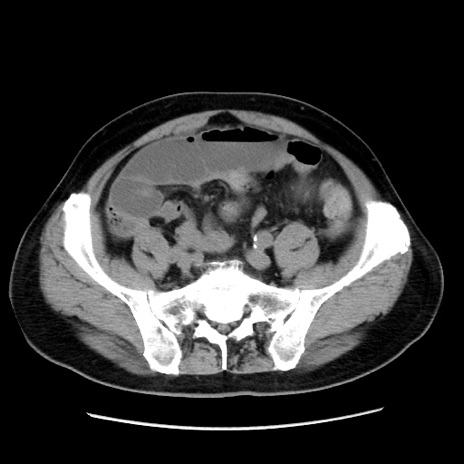

症例16(横断像)

【症例】 70歳代男性

【主訴】 腹痛、嘔吐

【現病歴】 約1ヶ月前より間欠的に腹痛と嘔吐あり、当院消化器内科を受診したところCTで多発する肝臓のLDAを指摘され、精査中であった。以降は消化器症状は安定していたが、2日前より嘔気と腹痛があり、同日より排便・排ガスが消失した。改善認めず、 本日、救急外来を受診した。

【既往歴】 大腸ポリープ切除後。

【身体所見】意識清明・会話良好、BT 36.3℃、BP 127/80mmHg、 P 80bpm、腹部:膨満あり、平坦・軟、上腹部正中および下腹部正中に圧痛あり、反跳痛なし、筋性防御なし。

【データ】WBC 7200、CRP 0.77